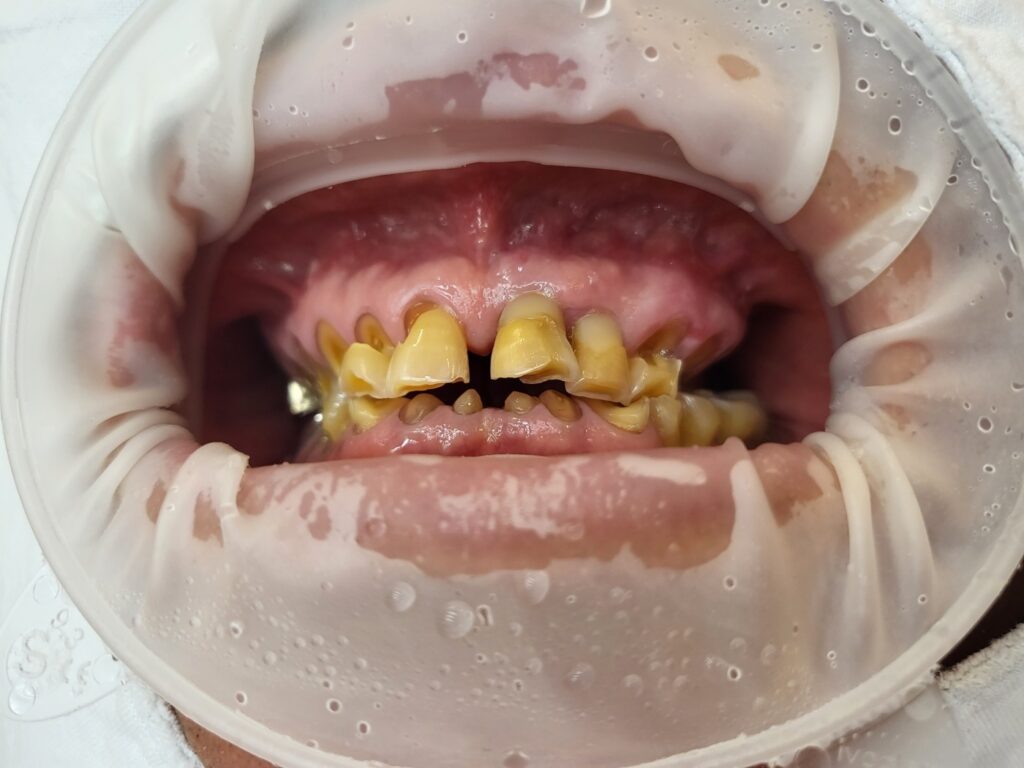

오늘 설명해 드릴 사례는 치아마모가 아주 심해 거의 대부분의 치아들이 뿌리만 남은 경우입니다. 치아마모는 치아교모라는 용어를 쓰기도 하는데요. 치아아 닳아서 크기가 줄어든 것을 말합니다.

치아마모가 있다고 다 뽑는 것은 아니지만 이렇게 뿌리만 남은 경우라면 뿌리를 살려서 치료를 하더라도 머리 부분에 문제가 반복적으로 생기기 때문에 전체적 발치 후 임플란트로 치료를 결정했어요.

치아마모는 엑스레이로 쉽게 보이지 않을 수 있습니다. 전문가는 엑스레이만으로도 마모를 볼 수 있지만 일반인은 엑스레이로 구분이 어려울 수 있어요. 위에 올려진 입 안 사진을 참고해 주세요.

아래쪽 어금니 중에 자신의 치아머리 부분이 어느 정도 남아있는 치아들은 발치하지 않고 크라운으로 치료를 하게 됩니다. 치아머리가 거의 없는 치아들은 치아를 씌운다고 해도 자꾸 탈락, 즉 빠지게 되므로 발치한 후 임플란트로 치료하게 됩니다.